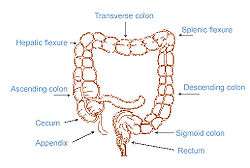

Colorectal anatomy (the splenic flexure is labeled at upper right, the hepatic flexure at upper left) | |

There are two colic flexures, or curvatures in the transverse colon. The one on the right, the right colic flexure is known as the hepatic flexure.

The one on the left, the left colic flexure is known as the splenic flexure.

The right colic flexure or hepatic flexure (as it is next to the liver) is the sharp bend between the ascending colon and the transverse colon. The hepatic flexure lies in the right upper quadrant of the human abdomen. It receives blood supply from the superior mesenteric artery.

The left colic flexure or splenic flexure (as it is close to the spleen) is the sharp bend between the transverse colon and the descending colon. The splenic flexure is a watershed region as it receives dual blood supply from the terminal branches of the superior mesenteric artery and the inferior mesenteric artery, thus making it prone to ischemic damage in cases of low blood pressure because it does not have its own primary source of blood. In the context of ischemia, the splenic flexure is sometimes referred to as Griffith's point, along with the upper rectum (Sudak's point).